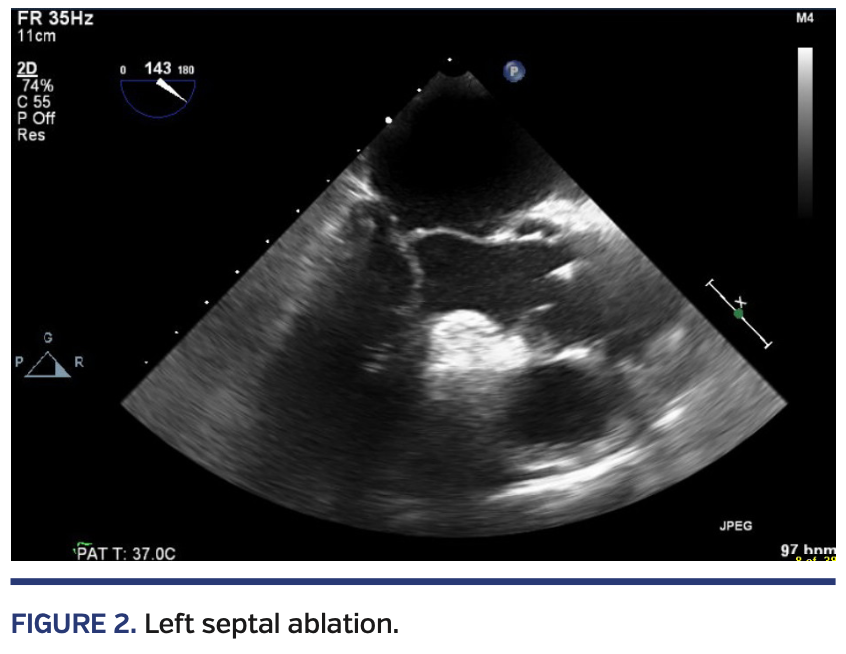

Left heart catheterization confirmed the presence of left ventricle-aorta pressure gradient (Figure 1) and showed septal perforators originating from the proximal segment of the right coronary artery (RCA), as well as the left anterior descending artery (LAD) (Videos 1 and 2). A guiding catheter was used to engage the left main coronary artery, and a coronary wire was passed into the LAD septal perforator. An over-the-wire balloon was then advanced. Contrast injection into the balloon catheter showed enhancement of the subaortic part of the septum on transesophageal echocardiography (TEE) (Figure 2). Alcohol was then injected. Postablation Doppler echocardiography showed a residual left ventricle-aorta pressure gradient of 40 mm Hg with no improvement in SAM. The guiding catheter was then withdrawn.